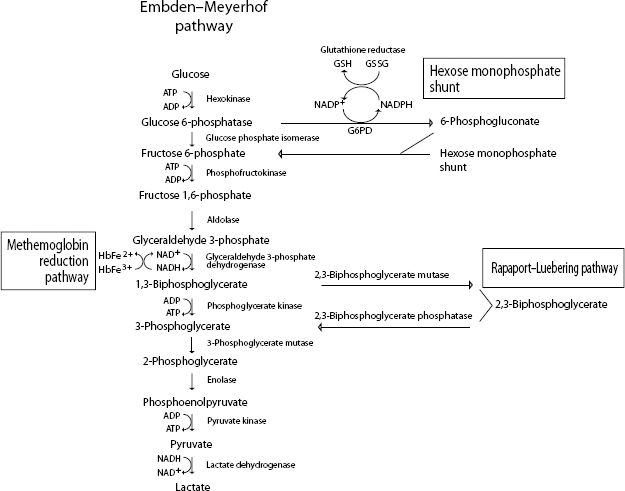

When reticulocytes mature and lose their mitochondria, they are no longer capable of oxidative metabolism. Mature erythrocytes derive their energy from adenosine triphosphate (ATP) generated by anaerobic glycolysis (Embden–Meyerhof pathway) (Fig. 1.26). ATP provides the energy to maintain membrane ion pumps. Defects in this pathway lead to an inability to maintain normal fluid and electrolyte content within the red cells, resulting in intravascular hemolysis or premature destruction in the spleen. Enzyme defects within a branch of the Embden–Meyerhof pathway, called the Rapaport–Luebering pathway, result in decreased production of 2,3-biphosphoglycerate (2,3-BPG, also known as 2,3-diphosphoglycerate, 2,3-DPG) with consequences of increased affinity of hemoglobin for oxygen and impaired oxygen delivery to tissues. In addition to generating ATP as an energy source, erythrocytes must be capable of preventing chemical injury (oxidative damage) from the high concentrations of oxygen that they transport. This is accomplished through two other branches of the Embden–Meyerhof pathway, the hexose monophosphate shunt and the methemoglobin reduction pathway. Glucose-6-phosphate is the substrate for the hexose monophosphate shunt which maintains glutathione in the reduced state. Reduced glutathione is an intracellular buffer that protects red cells from oxidant injury, particularly by hydrogen peroxide and the superoxide anion, and also helps to stabilize the reactive sulfhydryl groups of hemoglobin. The methemoglobin reduction pathway returns oxidized hemoglobin (methemoglobin) to its reduced state (ferrous/Fe2+) that is capable of oxygen transport.

Defects in the Embden–Meyerhof pathway that lead to ATP deficiency are manifested as hemolytic anemia due to an inability to maintain normal water and electrolyte homeostasis. Nonspherocytic but rigid erythrocytes are removed in the exacting environment of the spleen. Defects in production of 2,3-BPG result in an increased affinity of oxygen for hemoglobin, impaired oxygenation of tissues, and erythrocytosis. Defects in the hexose monophosphate shunt lead to oxidative damage to erythrocytes, hemoglobin denaturation, and Heinz body hemolytic anemia. Errors in the methemoglobin reduction pathway prohibit reduction of oxidized hemoglobin. Erythrocytes are unable to transport oxygen and cyanosis develops.

Figure 1.26 Erythrocyte metabolism.